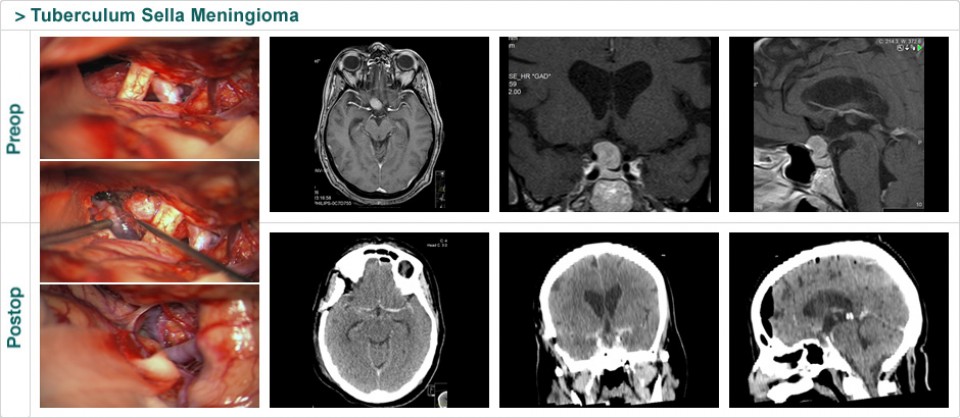

Dr. Attia is an attending neurosurgeon and the director of skull base surgery service in the department of neurosurgery at Sheba Medical Center in Tel HaShomer. His specialty focuses on skull base and cerebrovascular neurosurgery.